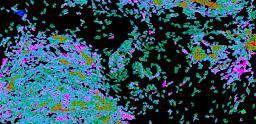

Pancreatic ductal adenocarcinoma is a lethal disease with limited treatment options and poor survival. We studied 83 spatial samples from 31 patients (11 treatment-naïve and 20 treated) using single-cell/nucleus RNA sequencing, bulk-proteogenomics, spatial transcriptomics and cellular imaging. Subpopulations of tumor cells exhibited signatures of proliferation, KRAS signaling, cell stress and epithelial-to-mesenchymal transition. Mapping mutations and copy number events distinguished tumor populations from normal and transitional cells, including acinar-to-ductal metaplasia and pancreatic intraepithelial neoplasia. Pathology-assisted deconvolution of spatial transcriptomic data identified tumor and transitional subpopulations with distinct histological features. We showed coordinated expression of TIGIT in exhausted and regulatory T cells and Nectin in tumor cells. Chemo-resistant samples contain a threefold enrichment of inflammatory cancer-associated fibroblasts that upregulate metallothioneins. Our study reveals a deeper understanding of the intricate substructure of pancreatic ductal adenocarcinoma tumors that could help improve therapy for patients with this disease.